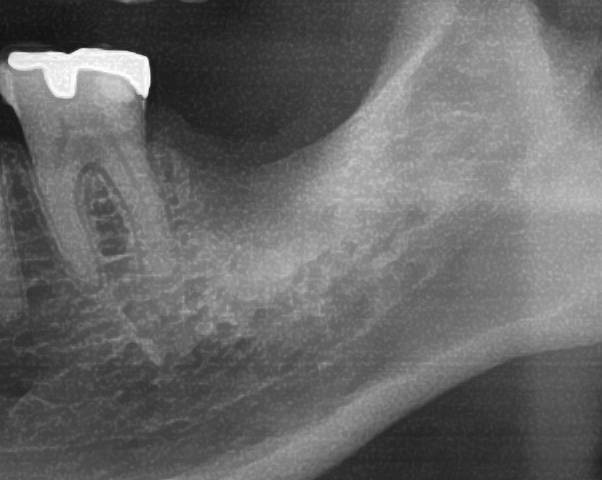

今回の患者様はインプラント植立を希望され、左下7番目の植立が決まりました。

しっかりとインプラント埋め込まれた後は、動揺がないか、噛んだ時に当たらないかなどを確認して、最後にパノラマ写真を撮影して今回のオペは終了となりました。